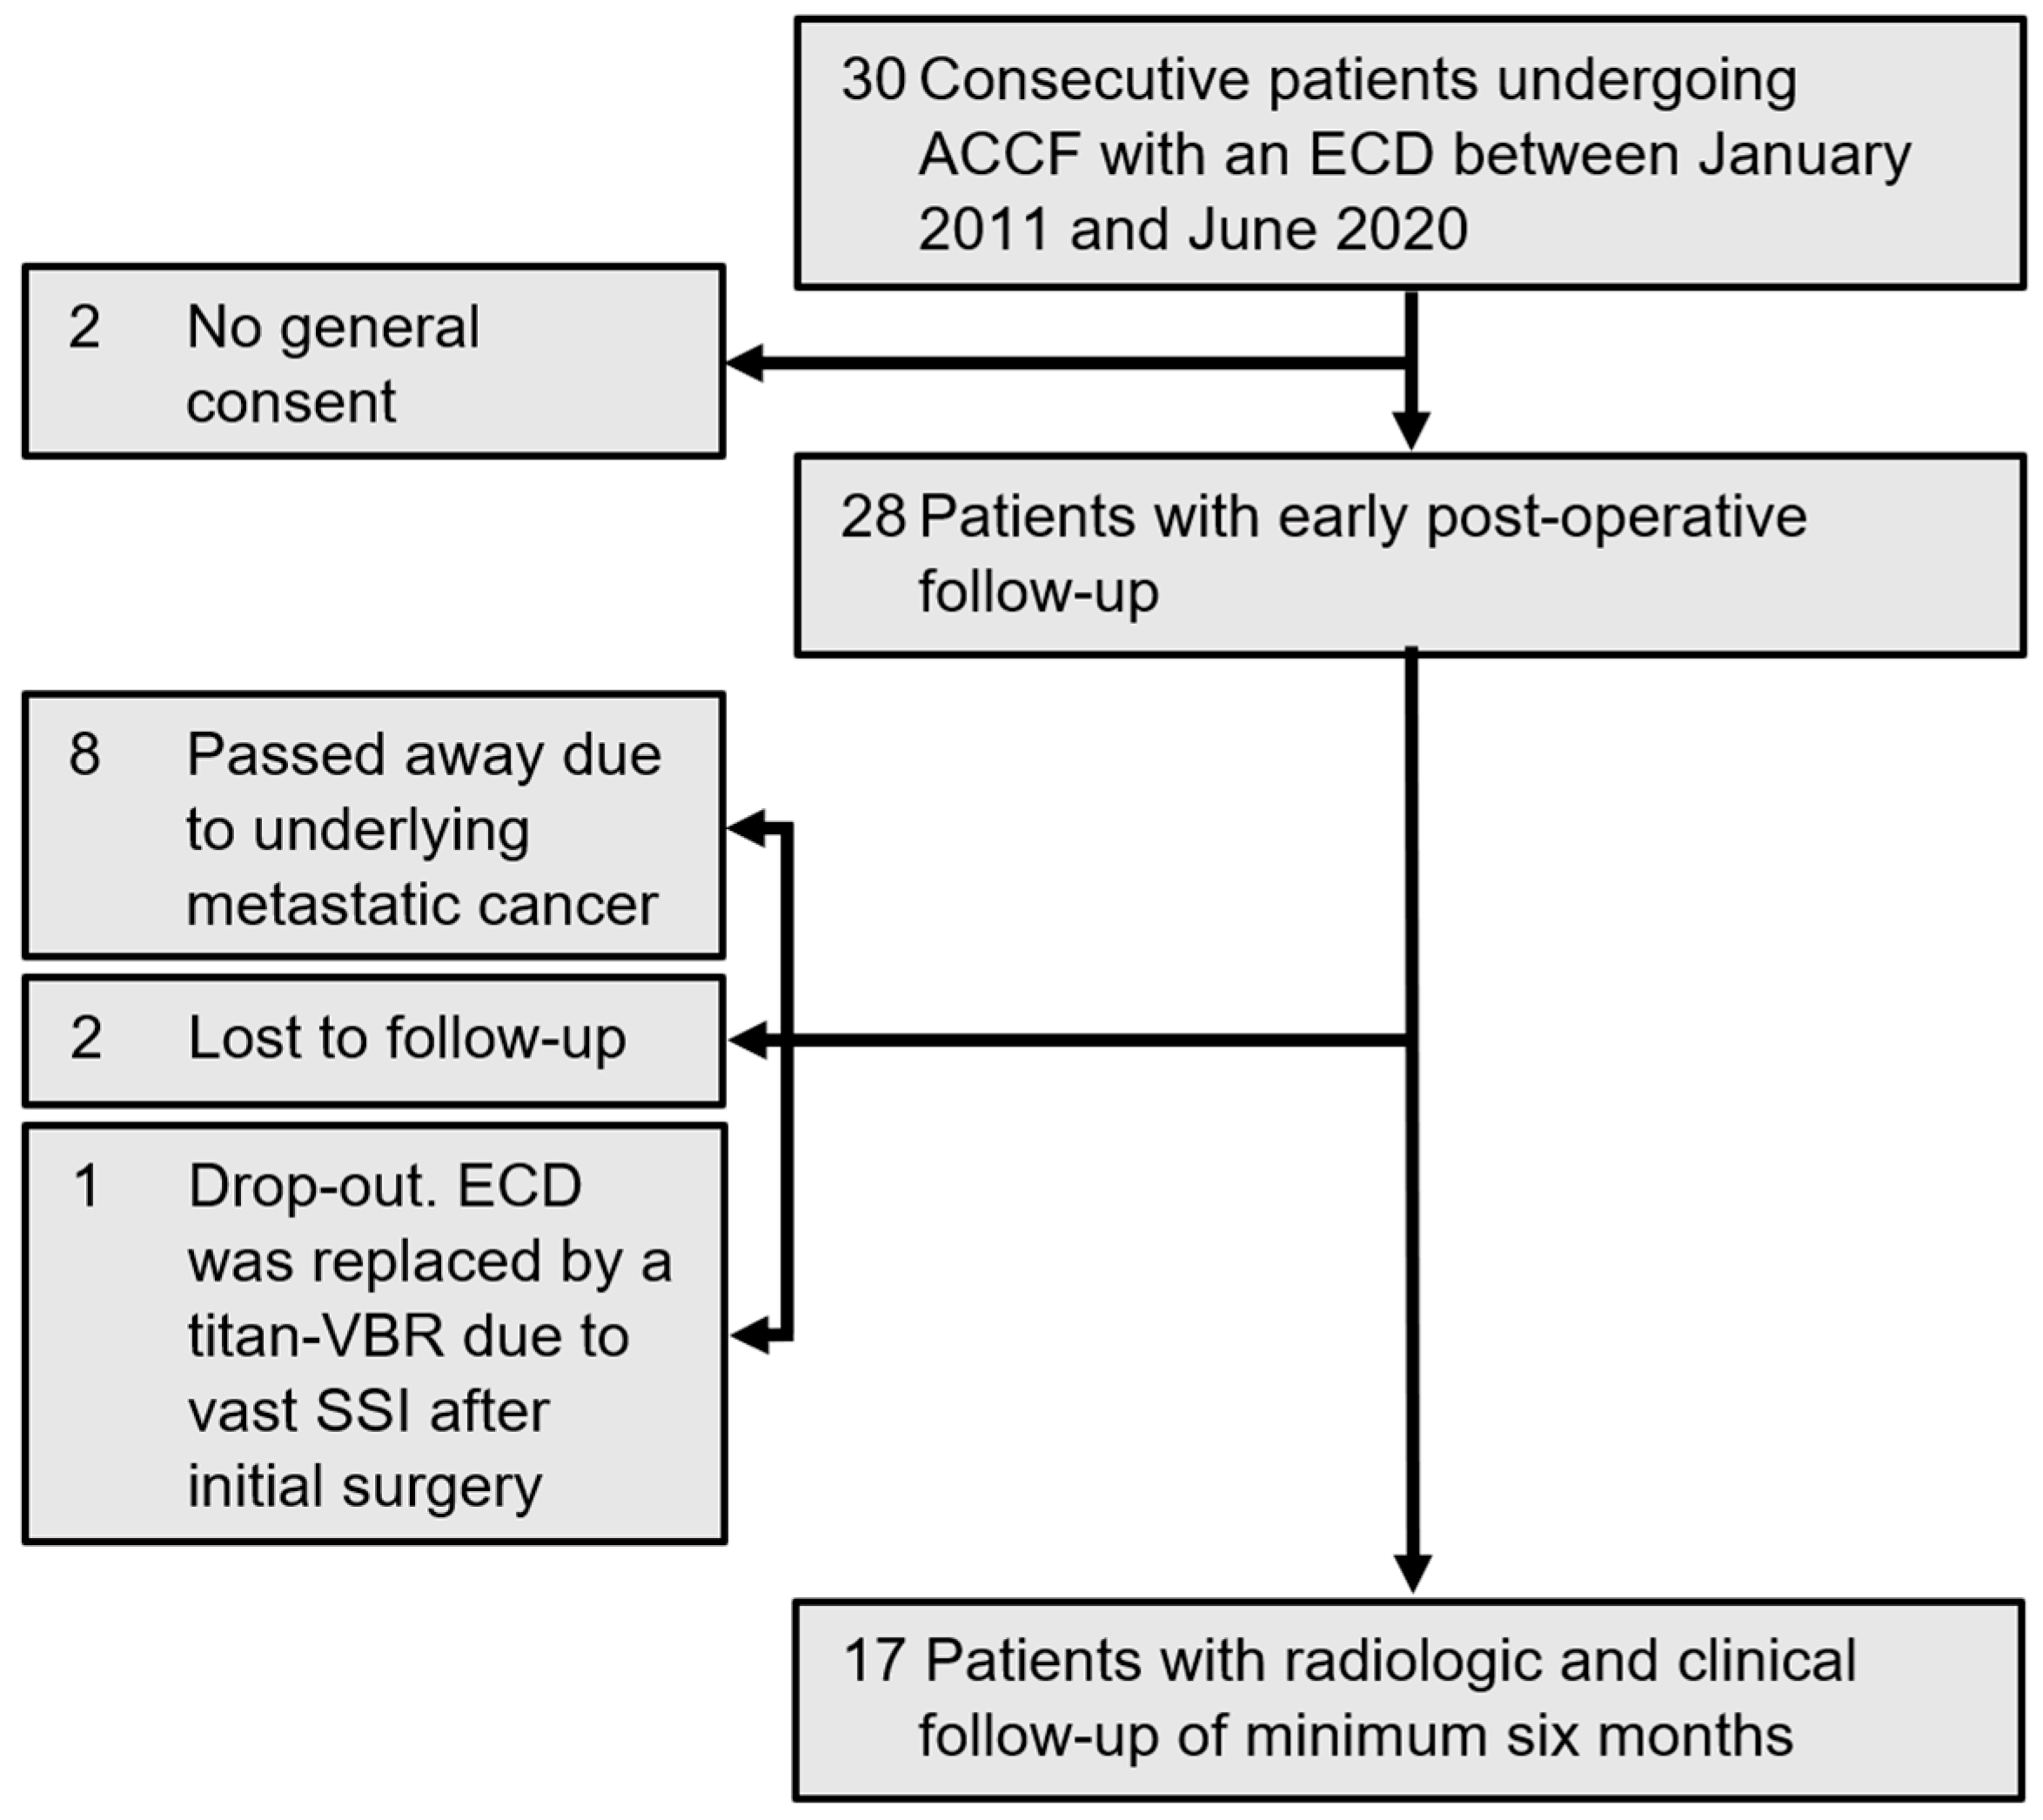

2.1. Study Population

2. Materials and Methods